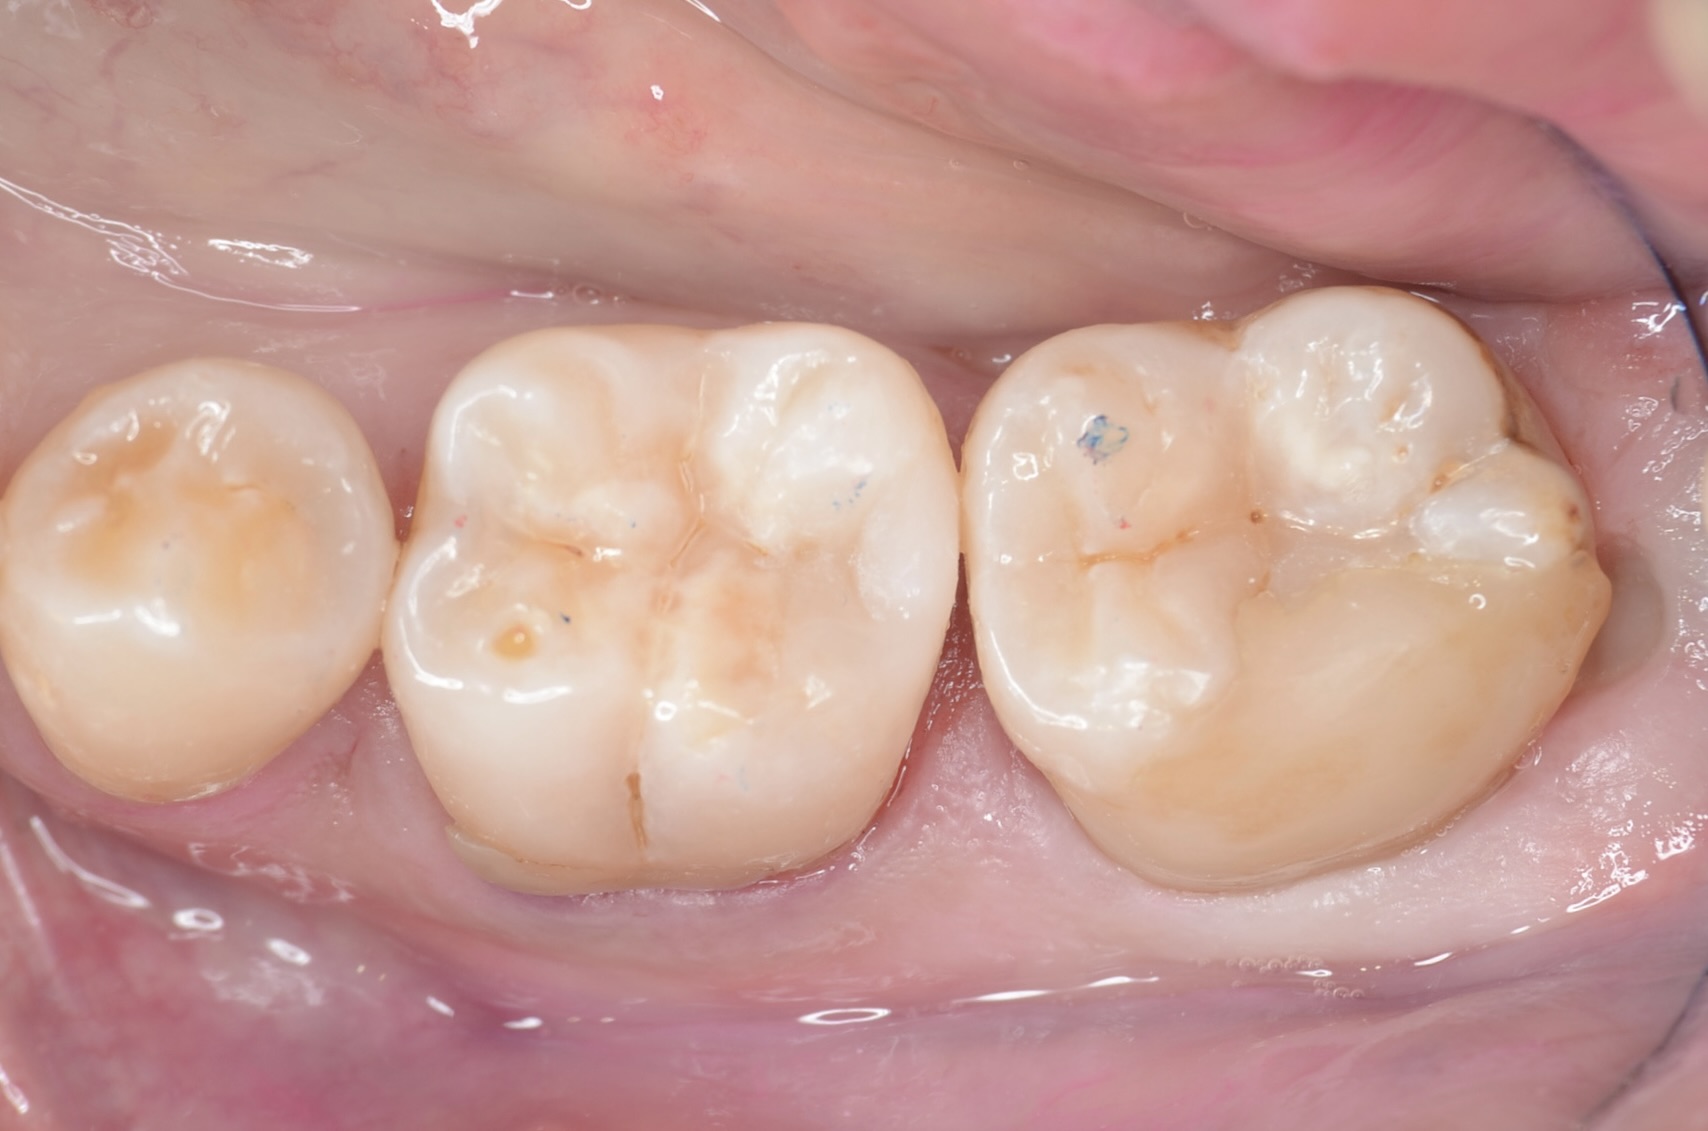

ダイレクトボンディング終了

ラバーダム撤去

歯と歯の間い隙間がありますが、すぐに閉じてきます。また5番と7番は次回以降治療します。 -

頬側面から見る

滑らかな段差の無い形態で形態に治す事ができました。